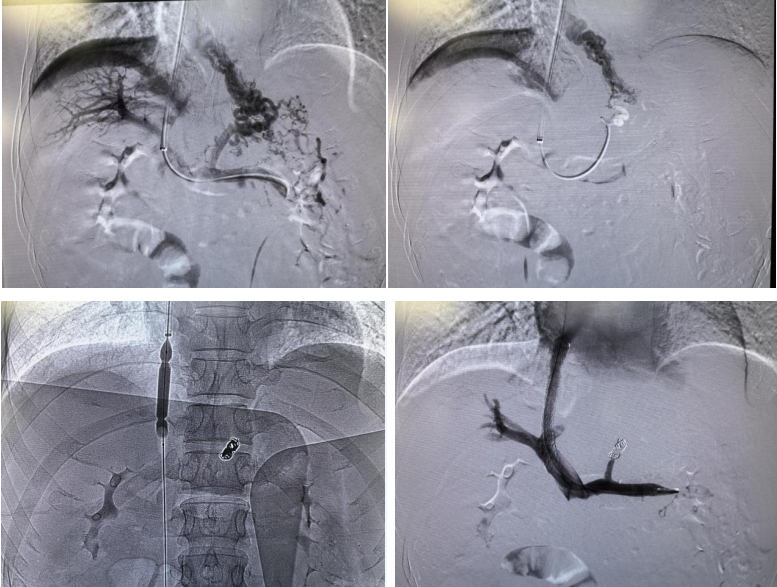

3月20日,经过充分的术前准备、术前检查及沟通,姚欣教授和孙邱主任成功为患者实施了TIPS术。术后,患者的门静脉压力梯度由术前的28cm水柱下降为13cm水柱,门静脉压力明显降低,达到了控制和预防食管胃底静脉曲张再次破裂出血的目的。